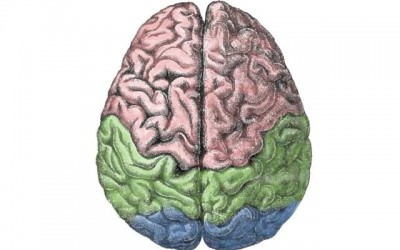

New Delhi, Feb 26 (IBNS): A diet created by researchers at Rush University Medical Center may help substantially slow cognitive decline in stroke survivors, according to preliminary research presented on Jan. 25 at the American Stroke Association’s International Stroke Conference 2018 in Los Angeles.